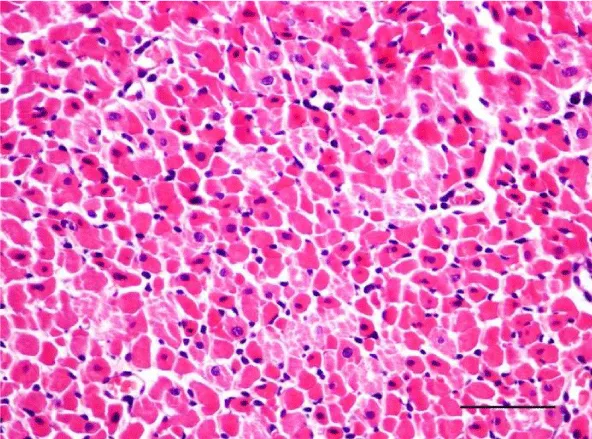

In the age groups of young rats (1- and 3-month-old), the H&E stain revealed a well-developed morphological organization of the layers of the myocardium in both ventricles. Bundles of longitudinally aligned cardiomyocytes were clearly observed, as well as subepicardial and subendocardial layers of transversely cut cardiac muscle cells. On a longitudinal section, cardiomyocytes from the left and right ventricle appeared eosinophilic, with cross striations and had one or two centrally located basophilic nuclei. The myofibrils appeared to be surrounding the nucleus and quite often, striations were noted in the perinuclear zone. The cardiomyocytes branched and formed anastomoses thus participating in a complex network. Each individual muscle fiber was enveloped by endomysium made up of fine connective tissue and perimysium with an abundant capillary network. Individual fibers were not always visualized but nuclei of fibroblasts and fibrocytes were identified among the cardiac muscle cells. The nuclei of the fibroblasts and fibrocytes were flat and stained more intensively than those of cardiomyocytes.

On a transverse section, the nuclei of the cardiomyocytes were centrally located and we observed that sometimes the perinuclear zone stained slightly more palely. Between the bundles of cardiac muscle cells we noted the presence of connective tissue, among which the nuclei of fibroblasts and fibrocytes were found. Some of them were located along the periphery of the muscle fiber due to each individual cardiomyocyte being enveloped by endomysium. Multiple capillaries were observed as small optically empty oval structures around the cardiomyocytes. The thickened areas of the capillary wall marked the location of the nuclei of the endothelial cells. Large intramural blood vessels were also seen, in the lumen of which we noted the presence of erythrocytes (Figures 5-8).